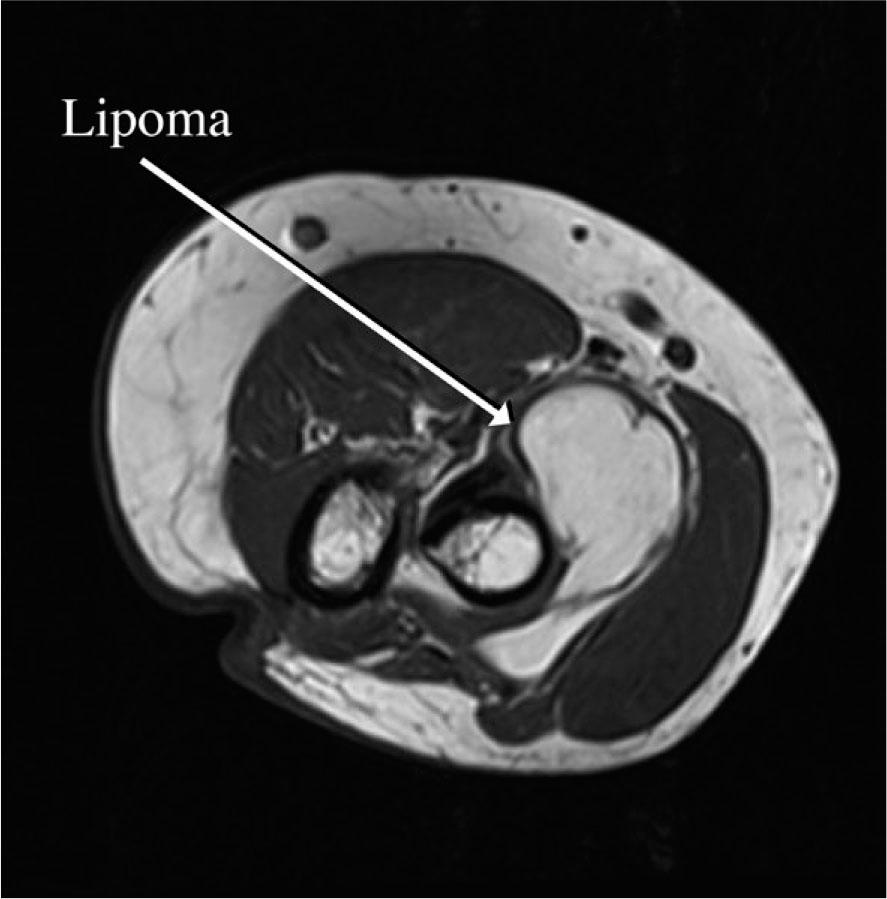

FIGURE 1.